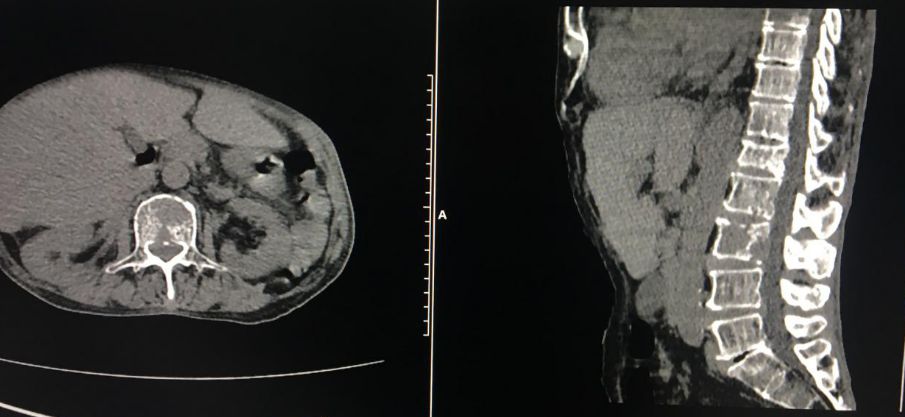

全新日本进口佳能金刚螺旋CT

该新设备功能先进,有平扫、三维重建、X线计算机体层成像等功能,能对人的头部、颈部、胸腔、四肢、盆腔等多个部位进行扫描成像。

现在医院引进了全新的进口螺旋CT,患者直接就能在医院确诊,节约了患者的时间,并且,进口的螺旋CT机扫描图像质量好,显示清晰。

该设备自运行以来,发现并确诊不少疾病:颈椎椎间盘突出、 腰椎椎间盘膨出伴双侧神经根受压、硬膜外血肿、右侧上颌窦炎、右侧筛窦炎、双肺感染伴双侧胸腔积液、心包积液、右侧胸腔包裹性积液、原发性肝癌伴骨转移等疾病。